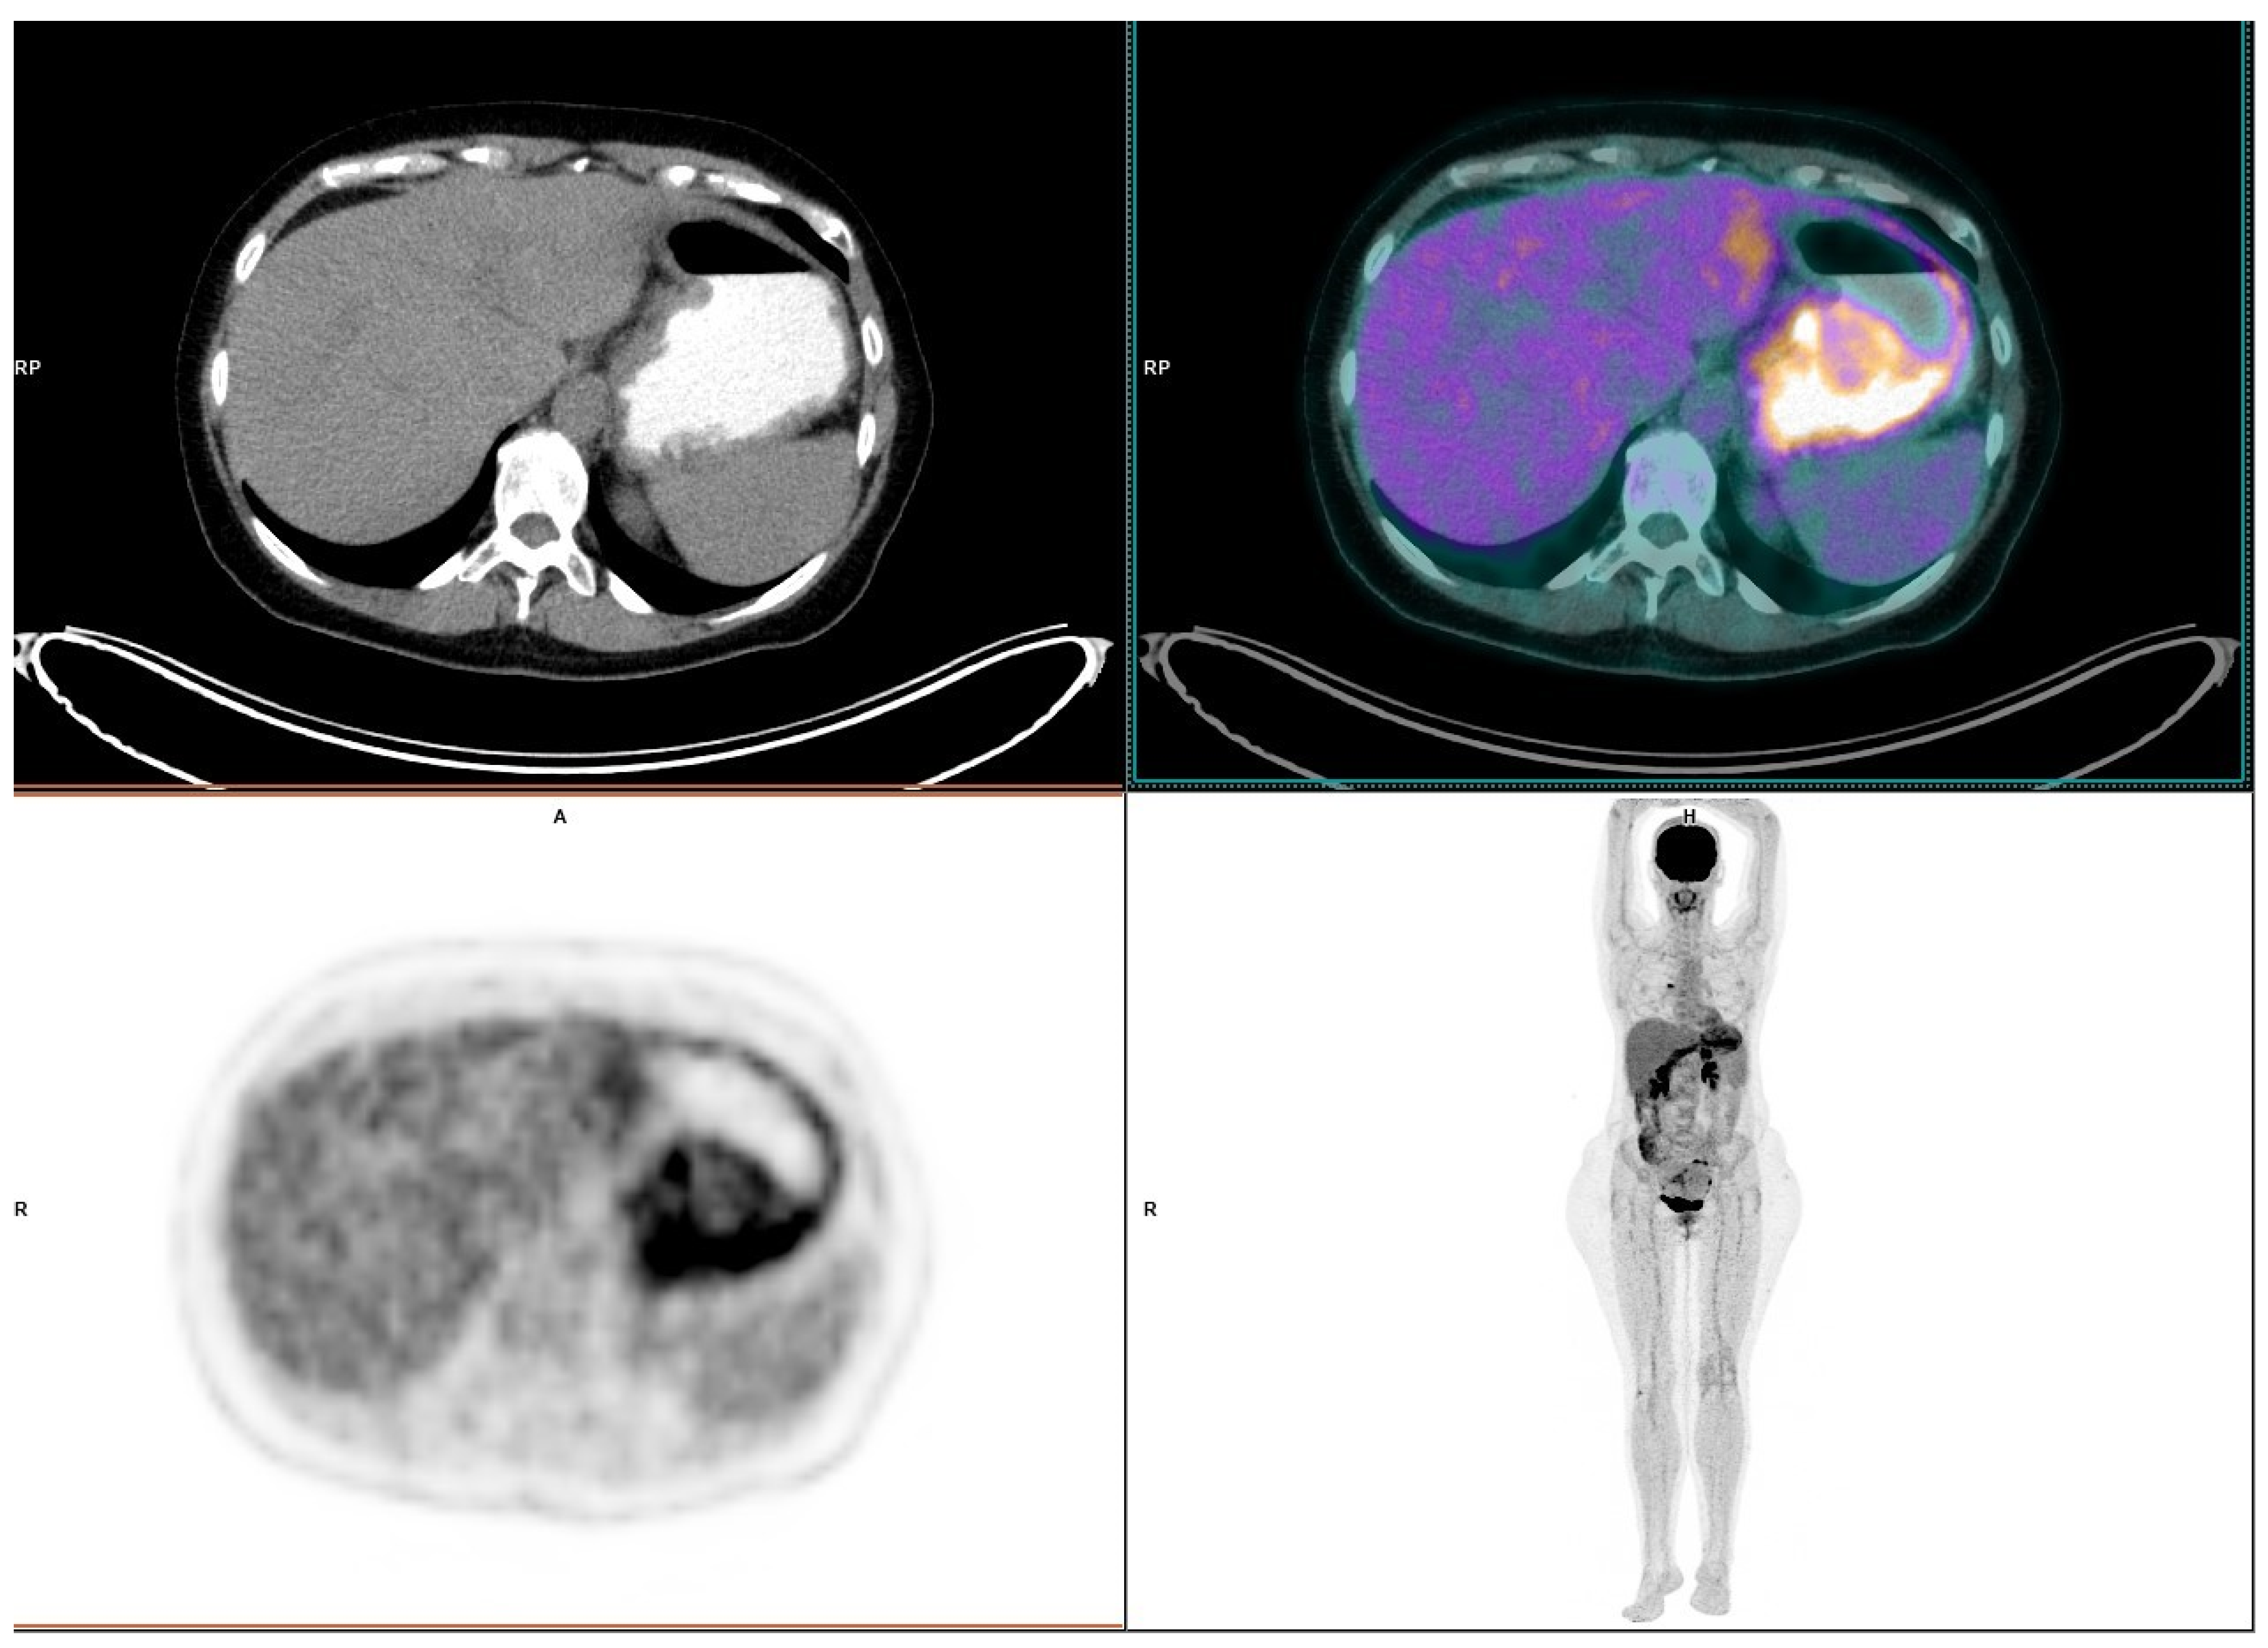

Severe Gastritis Due to Nivolumab Treatment of a Metastatic Melanoma Patient

2. Case Presentation